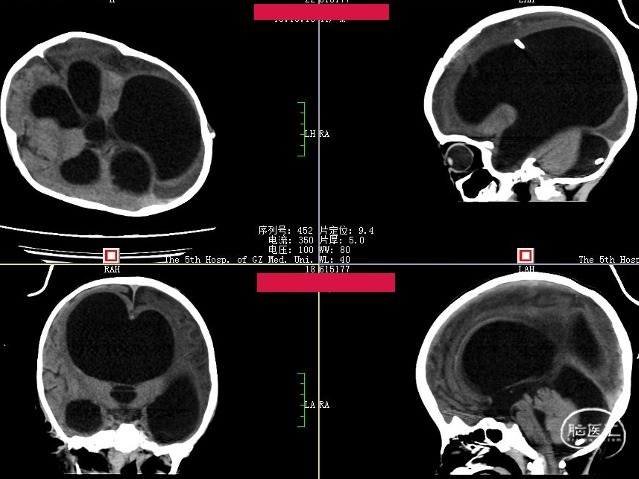

术后CT(2周)

Evans index(EI)≈0.50

脑积水缓解,脑皮质较前变厚,症状较前好转。